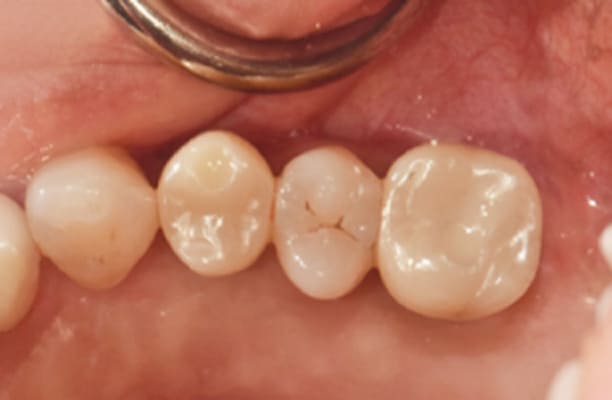

临床案例

-

术前 -

术后